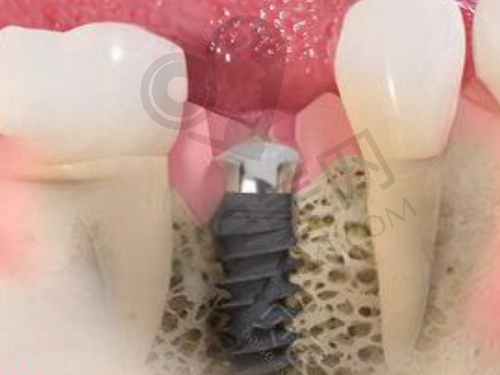

在牙齿种植方面,优佳贝口腔同样表现出色。医院引进了国内外新型的口腔诊疗设备,如数字影像系统、微痛麻醉技术等,确保治疗的精细性和可靠性。种植总监梁照忠院长在种植牙方面具有较高的技术水平,能够接诊复杂的种植手术,如植骨手术、上颌窦内外提升术等。